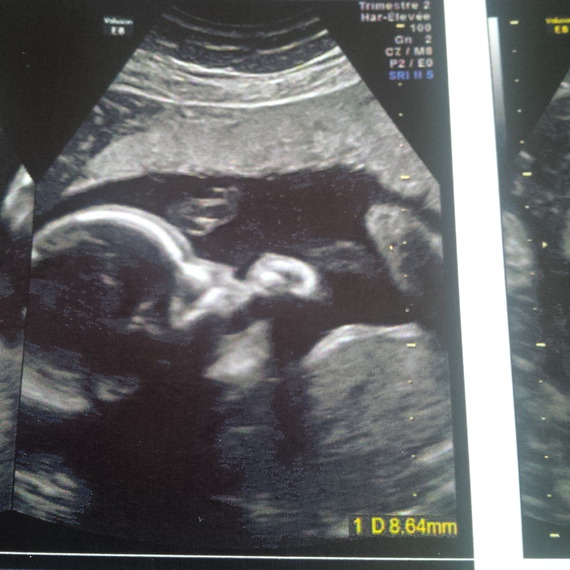

Echographie bebe bouche ouverte-Je viens poster ici en espèrant que vous saurez me rassurer Il s'agit de ma petite soeur qui est enceinte pour novembre, à l'échographie du second trimestre, on a vu que la bouche de sa petite était toujours ouverte, on n'a pas mesuré la clarté nuquale (au premier trimestre, elle faisait 12) L' endoscopie digestive haute est l'observation de l'intérieur de l'œsophage, de l'estomac et du duodénum (première partie de l'intestin grêle) Cet examen est également nommé "endoscopie œsogastroduodénale" ou "fibroscopie œsogastroduodénale", "gastroscopie"On réalise cet examen grâce à un endoscope ou gastroscope introduit par la bouche ou le nez

Vincent était ravi, on s'est tenu la main fort fort, j'ai encore pleuré un peu au début Puis j'ai profité du scénario, des plans séquences On l'a vu ouvrir et fermer la bouche On a bien vu ses yeux, ses mains, doigts de pieds L'infirmière était super !!Quand le bébé tire la langue, il ouvre sa bouche et de la salive peut glisser sur son menton "C'est ce qu'on appelle le bavage" indique Gaëlle Malécot Cette émission involontaire de salive par la bouche est normale chez le bébé et disparaît normalement avant l'âge de 3 ou 4 ans Echographie connaître le sexe de votre bébé J'en ai une où on voit bien le nez et bouche ouverte avec petit bout de langue 🤣 Ton écho à l'air semblable !

Lors de ma dernière échographie (29 SA) ma gynécologue a pu constater que mon bébé, encore une fois, avait la bouche ouverte et interposait souvent sa langue entre ses deux lèvres Lors de l'échographie précédente, il avait déjà la bouche ouverteLe seconde échographie de grossesse, dite échographie morphologique, est une étape importante du suivi de grossesse car elle permet de déceler d'éventuelles malformations fœtales Les mouvements enregistrés par échographie et comme signe d'un bébé qui pleure sont sa bouche ouverte, sa langue baissée, son menton vibrant et sa respiration devenant irrégulière Les différentes expressions sur le visage de Si Kecil, y compris les pleurs, peuvent être vues lorsque Bunda effectue un examen échographique de la grossesse